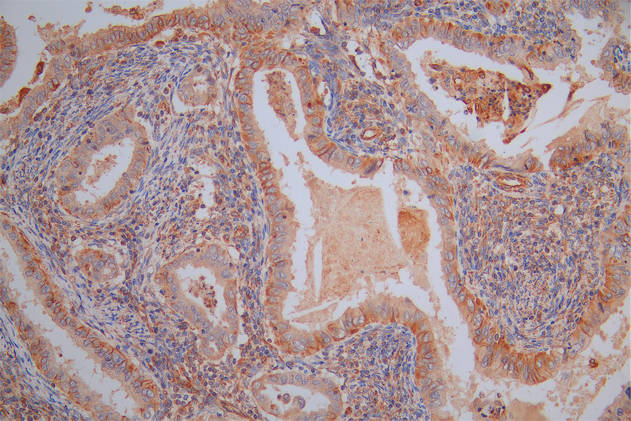

IHC image of CSB-PA008727LA01HU diluted at 1:100 and staining in paraffin-embedded human cervical cancer performed on a Leica BondTM system. After dewaxing and hydration, antigen retrieval was mediated by high pressure in a citrate buffer (pH 6.0). Section was blocked with 10% normal goat serum 30min at RT. Then primary antibody (1% BSA) was incubated at 4°C overnight. The primary is detected by a biotinylated secondary antibody and visualized using an HRP conjugated SP system.

IHC image of CSB-PA008727LA01HU diluted at 1:100 and staining in paraffin-embedded human kidney tissue performed on a Leica BondTM system. After dewaxing and hydration, antigen retrieval was mediated by high pressure in a citrate buffer (pH 6.0). Section was blocked with 10% normal goat serum 30min at RT. Then primary antibody (1% BSA) was incubated at 4°C overnight. The primary is detected by a biotinylated secondary antibody and visualized using an HRP conjugated ABC system.